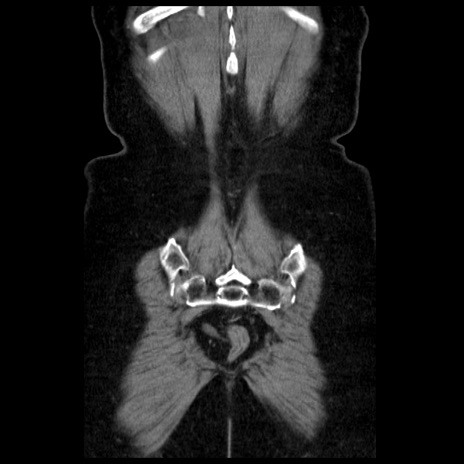

横断像